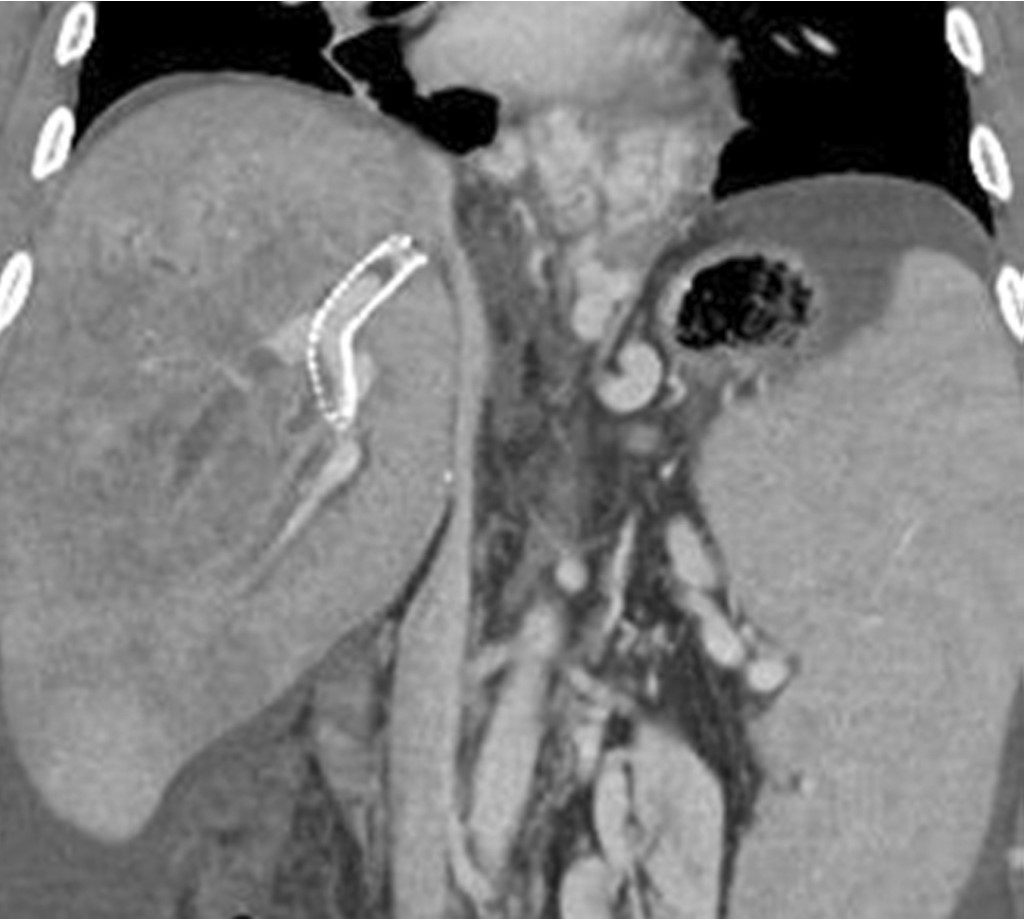

생체간이식 수술 1년 후 시행한 복부 CT에서 우간정맥 (right hepatic vein)은 개통되어 있으나 5번 분절(sgment)과 8번 분절 간정맥을 하대정맥과 연결하는 이식혈관은 폐색되어 있으며 문맥압항진증으로 인해 복수가 증가하였음. 목정맥경유간생검 조직검사에서 만성거부반응이 나왔음. 난치성 복수와 식도정맥류 출혈의 치료를 위해 TIPS를 시행하였음. TIPS시술 6일 후 시행한 복부 CT에서 TIPS 경로의 원위부에 부분 폐색이 관찰되며 우간정맥 혈전증에 의한 간 울혈의 소견으로 불규칙한 저음영 병변들이 관찰됨 (Fig 1).

Fig. 1.

CT scan obtained on 6 days after TIPS show partial occlusion of distal end of the TIPS stent, and ill defined low density in the liver due to hepatic vein thrombosis.